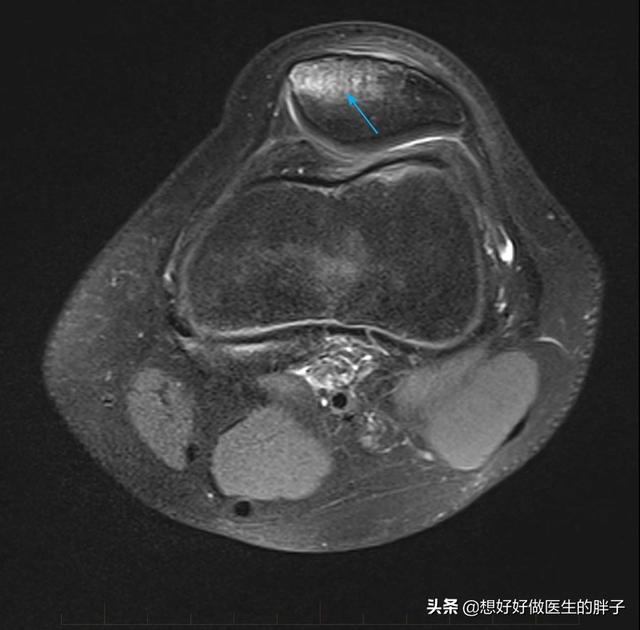

髌骨挫伤在临床上是相对来讲比较常见的,这种损伤机制多见于在运动过程当中摔倒膝盖着地,髌骨与地面相撞的过程当中虽然*力暴**没有导致整个髌骨的离断,但是导致髌骨内发生了细小的骨折,我们称之为微骨折,这种情况在核磁上表现出来的影像学表现称之为骨挫伤,下图就是典型的髌骨挫伤的影像学表现。

骨挫伤 箭头所指为明显挫伤区域,瘀血和水肿核磁表现

虽然*力暴**没有导致整个髌骨的骨折,但是*力暴**传导到髌骨内部以后,造成了髌骨内骨小梁的细小骨折,这样骨折以后就会有水肿、有出血,所以在核磁眼镜上是高亮的表现,在上图当中箭头所指的部位就是骨损伤的部位。